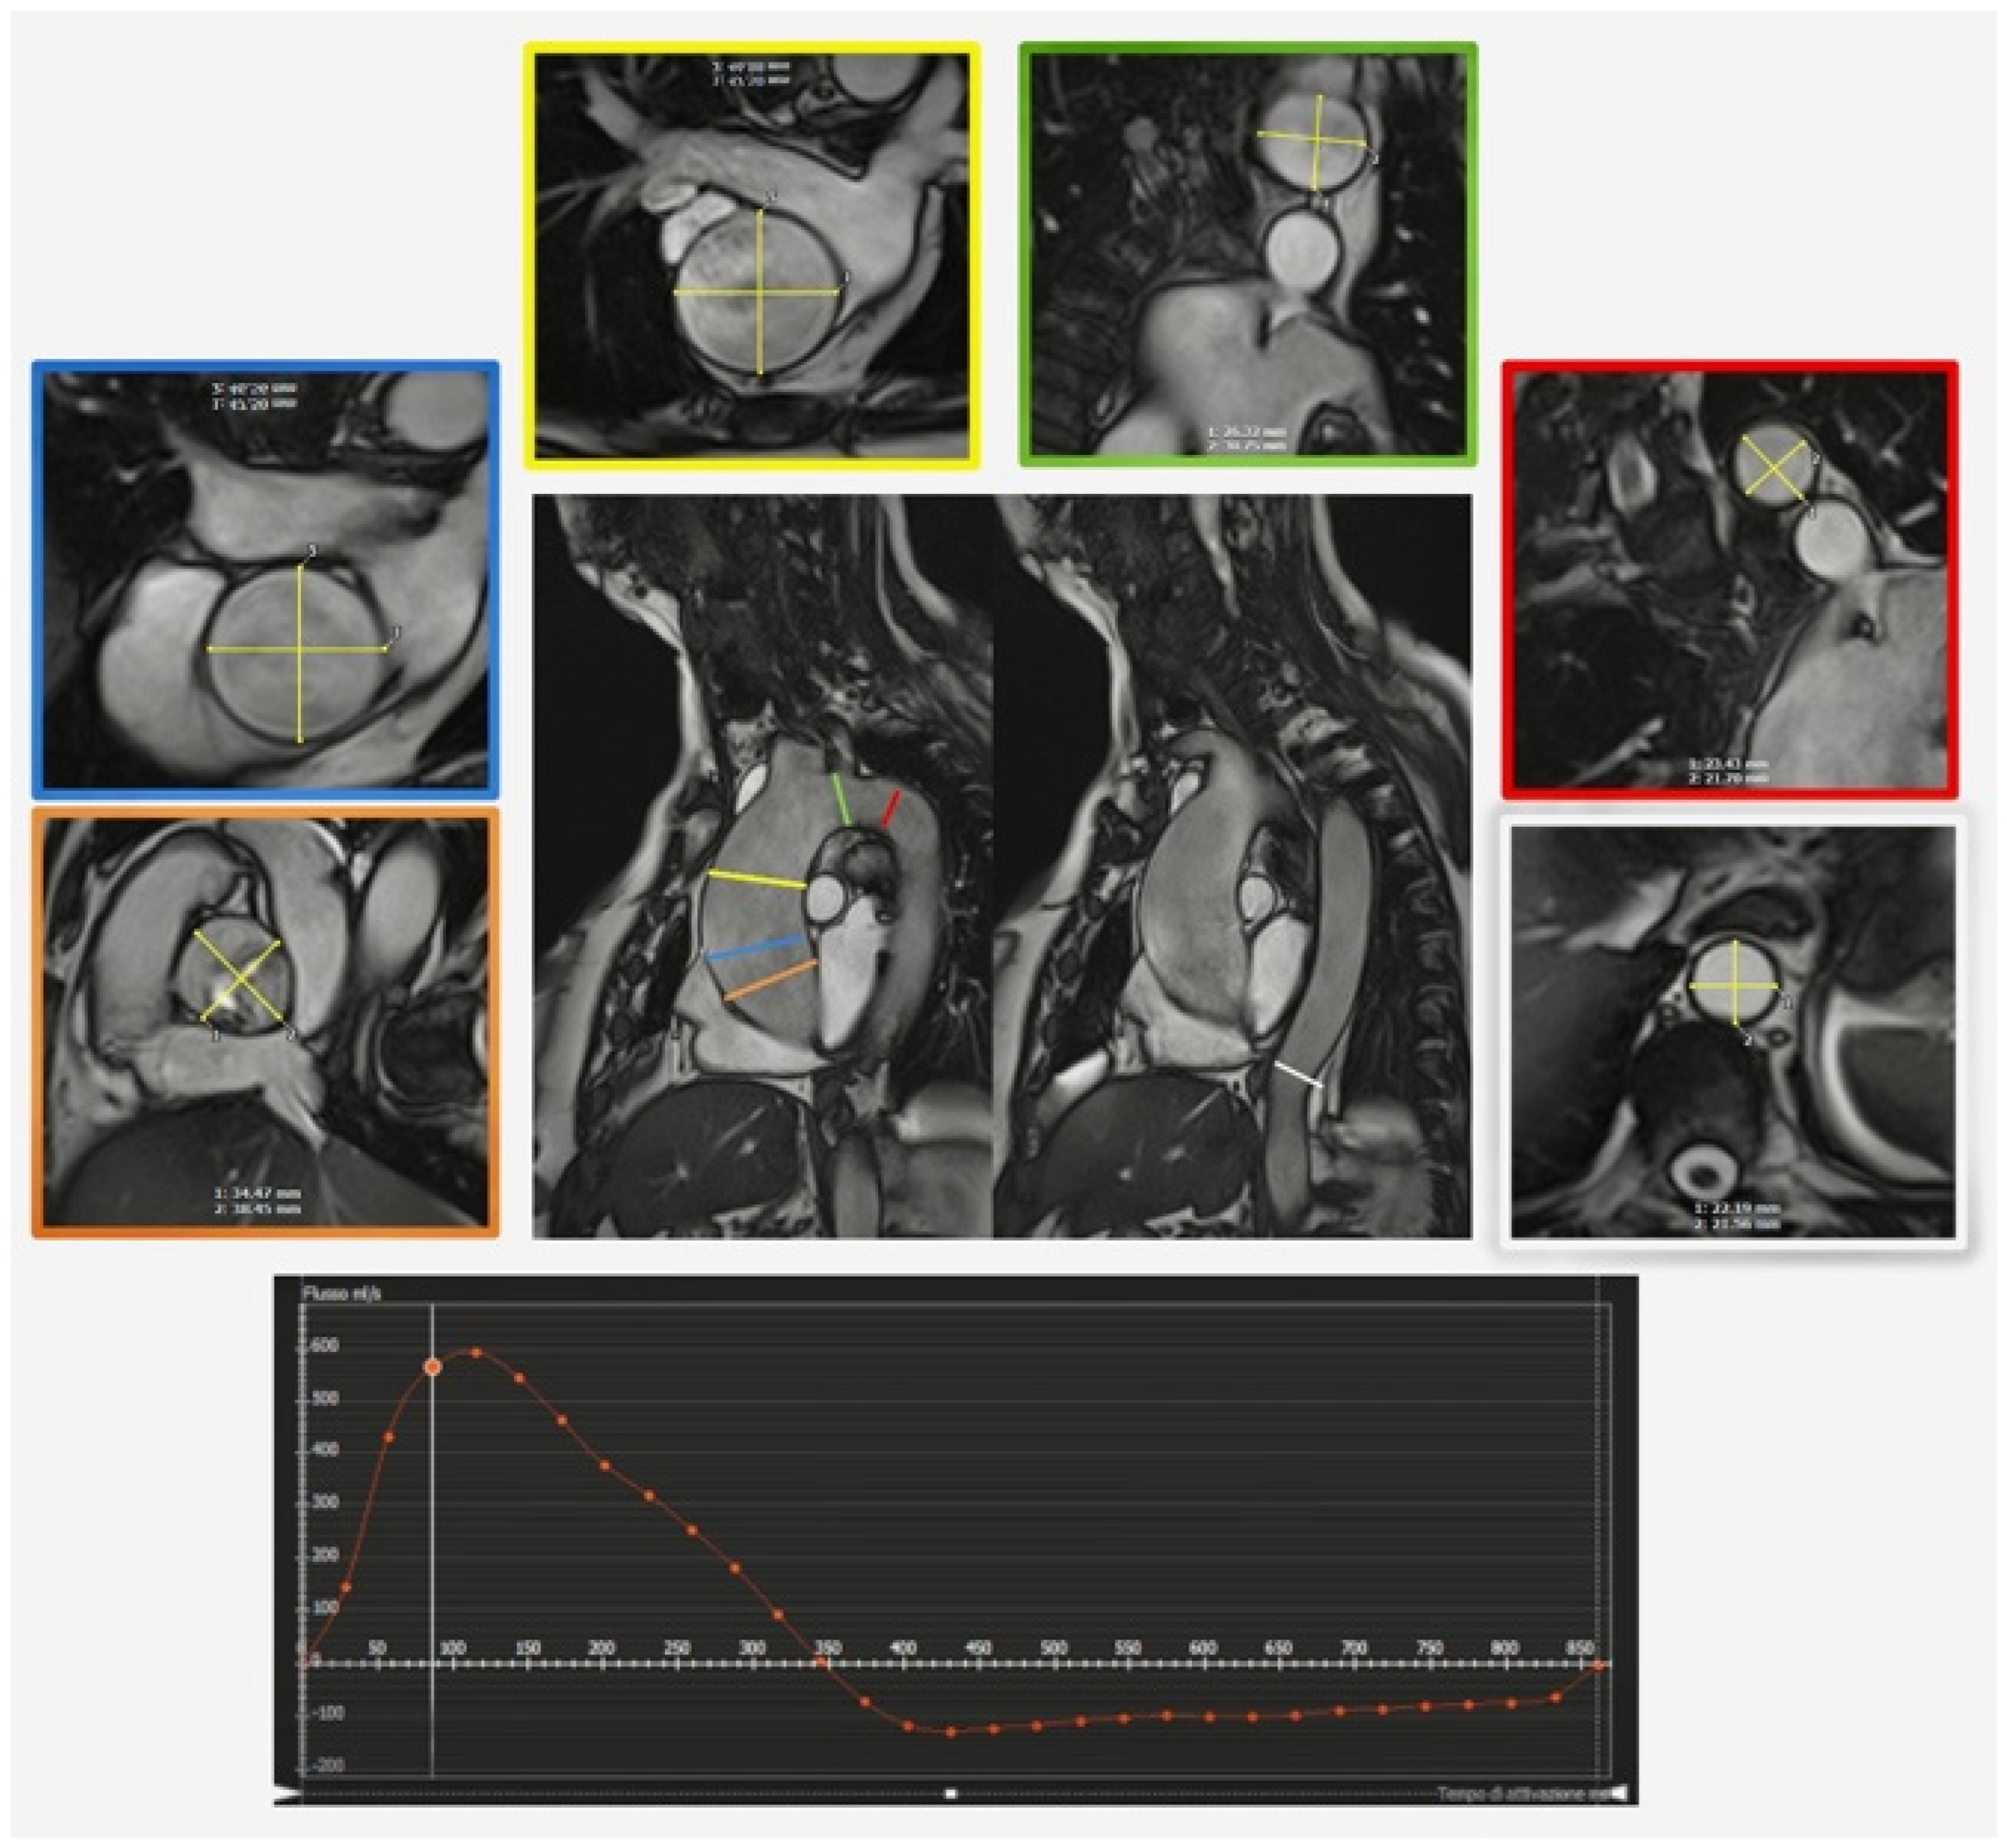

1.2. Magnetic Resonance